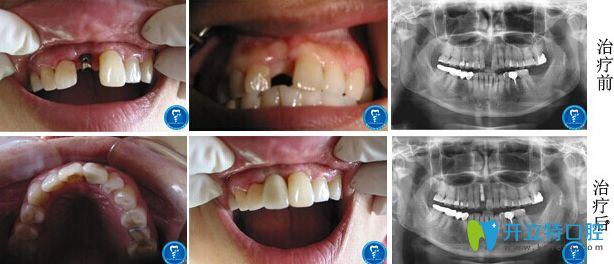

北京京通口腔怎么樣?張蓉醫(yī)生單顆牙缺失即刻種植修復(fù)前后對(duì)比圖:

種植牙前:意外導(dǎo)致上門(mén)牙斷掉半截,不但影響美觀,說(shuō)話(huà)還跑風(fēng);

種植牙后:在網(wǎng)上對(duì)北京京通口腔做了詳細(xì)的了解,才決定去做的種植牙修復(fù),即刻種植牙效果就是好,拔牙和種植牙全程用了不到兩個(gè)小時(shí),就重“新”長(zhǎng)出了牙齒,啃東西還有外觀都和真牙一模一樣!

北京京通口腔單顆牙缺失即刻種植案例